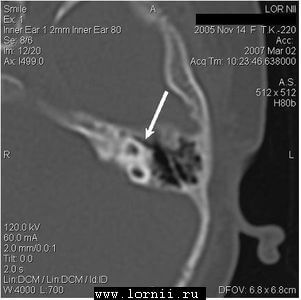

КТ височных костей выявила наличие двухсторонней аномалии развития улитки в виде неполного разделения I типа (табл. 4). При этом данное утверждение верно как для левого, так и для правого уха, несмотря на различную, на первый взгляд, картину (рис.1).

После обследования пациентке проведена КИ на левом ухе классическим доступом через антромастоидотомию и заднюю тимпанотомию, с введением электрода через кохлеостому. Для операции использовался специальный укороченный электрод (Med-El, Австрия), имеющий рабочую длину активного электрода около 12 мм, специально разработанный для применения в случаях аномалии или оссификации улитки.